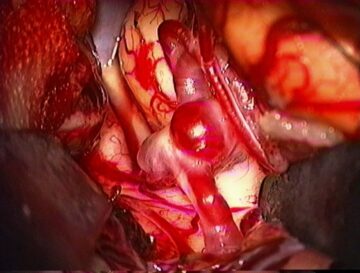

(3)くも膜下出血

脳の表面を覆っている「くも膜」の下にある太い血管が破裂して出血し、脳の表面全体に血液が広がってしまう状態です。

多くは「脳動脈瘤(りゅう)」という、脳の血管にできたコブの破裂が主な原因です。高血圧や喫煙、過度の飲酒が発症のリスクを高めるとされています。

今まで経験したことのない、突然の激しい頭痛が典型的な症状で「ハンマーで殴られたような」と表現されるほど強烈な痛みが特徴です。意識障害や吐き気を伴うこともあります。脳卒中の中で死亡率が最も高い病気の一つで、発症後数時間で命を落とす危険があります。